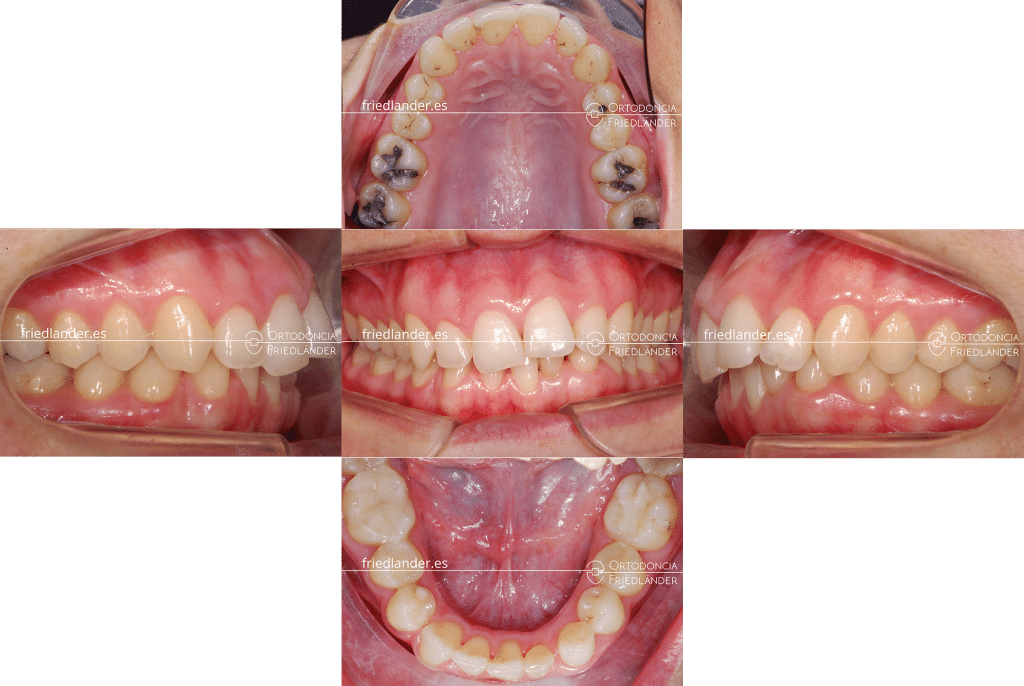

Esta entrada es sobre un tratamiento multidisciplinar de una paciente de 35 años que presenta agenesias de 3 dientes mandibulares. La agenesia dental es la falta de formación de algún diente, puede suceder por muchos motivos el principal de ellos es genético; en nuestro blog pronto publicaré una entrada más detallada y extensa sobre las agenesias dentales.

En este caso los dientes ausentes son dos incisivos inferiores del lado izquierdo y el canino inferior izquierdo. Estas agenesias son bastante raras ya que las más frecuentes son de las muelas de juicio, incisivos laterales superiores y segundos premolares inferiores (los casos 16 y 17 son dos tratamientos de agenesias de segundos premolares inferiores solucionados de dos maneras diferentes). En la primera visita, la paciente nos comenta y le preocupa que algún diente de leche, todavía presente en boca, tiene movilidad, tiene miedo de perderlo y quedarse con un hueco entre los dientes. Normalmente la presencia de un diente de leche en la edad adulta nos puede indicar que el diente definitivo que le sigue está ausente. Mediante una radiografía panorámica (una ortopantomografía) se diagnostica rapidamente las agenesias que tiene la paciente.

El tratamiento de las agenesias dentales implica un tratamiento multidisciplinar, un tratamiento donde intervienen varios profesionales para poder dar solución al problema que presneta la paciente, sobretodo si las agenesias son de dientes anteriores. La solución inmediata, pero no la mejor es la colocación de implantes. En un caso así la colocación de implantes sin planificación en equipo podría comprometer el resultado final del tratamiento.